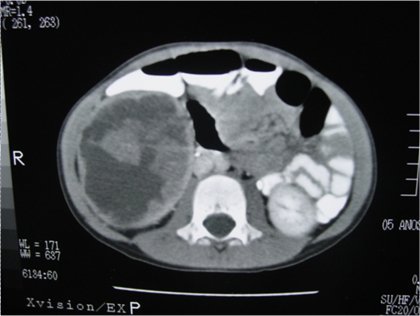

Case 1: A 7-year-old male, presented with gross hematuria for one week. Six months before he had fallen from a tree and was conservatively treated for renal trauma in another hospital, but lost follow-up. He had a painless abdominal mass on the right flank. CT showed an abnormal kidney, suspicious of renal tumor/ urinoma (Figure-1). Laparotomy was performed, due to gross hematuria, and a ruptured tumor of the upper pole of the right kidney was found. Nefrectomy was performed, as well as surgical staging of the tumor. Postoperative period was uneventful. Pathology revealed an anaplastic Wilms tumor and postoperative staging showed a pulmonary metastasis, thus the patient was staged IV. Patient was alive and well until three years after surgery. Follow up was lost afterwards.

Figure 1 - CT of case 1: a large renal mass due to Wilms tumor, with intratumoral hemorrhage.